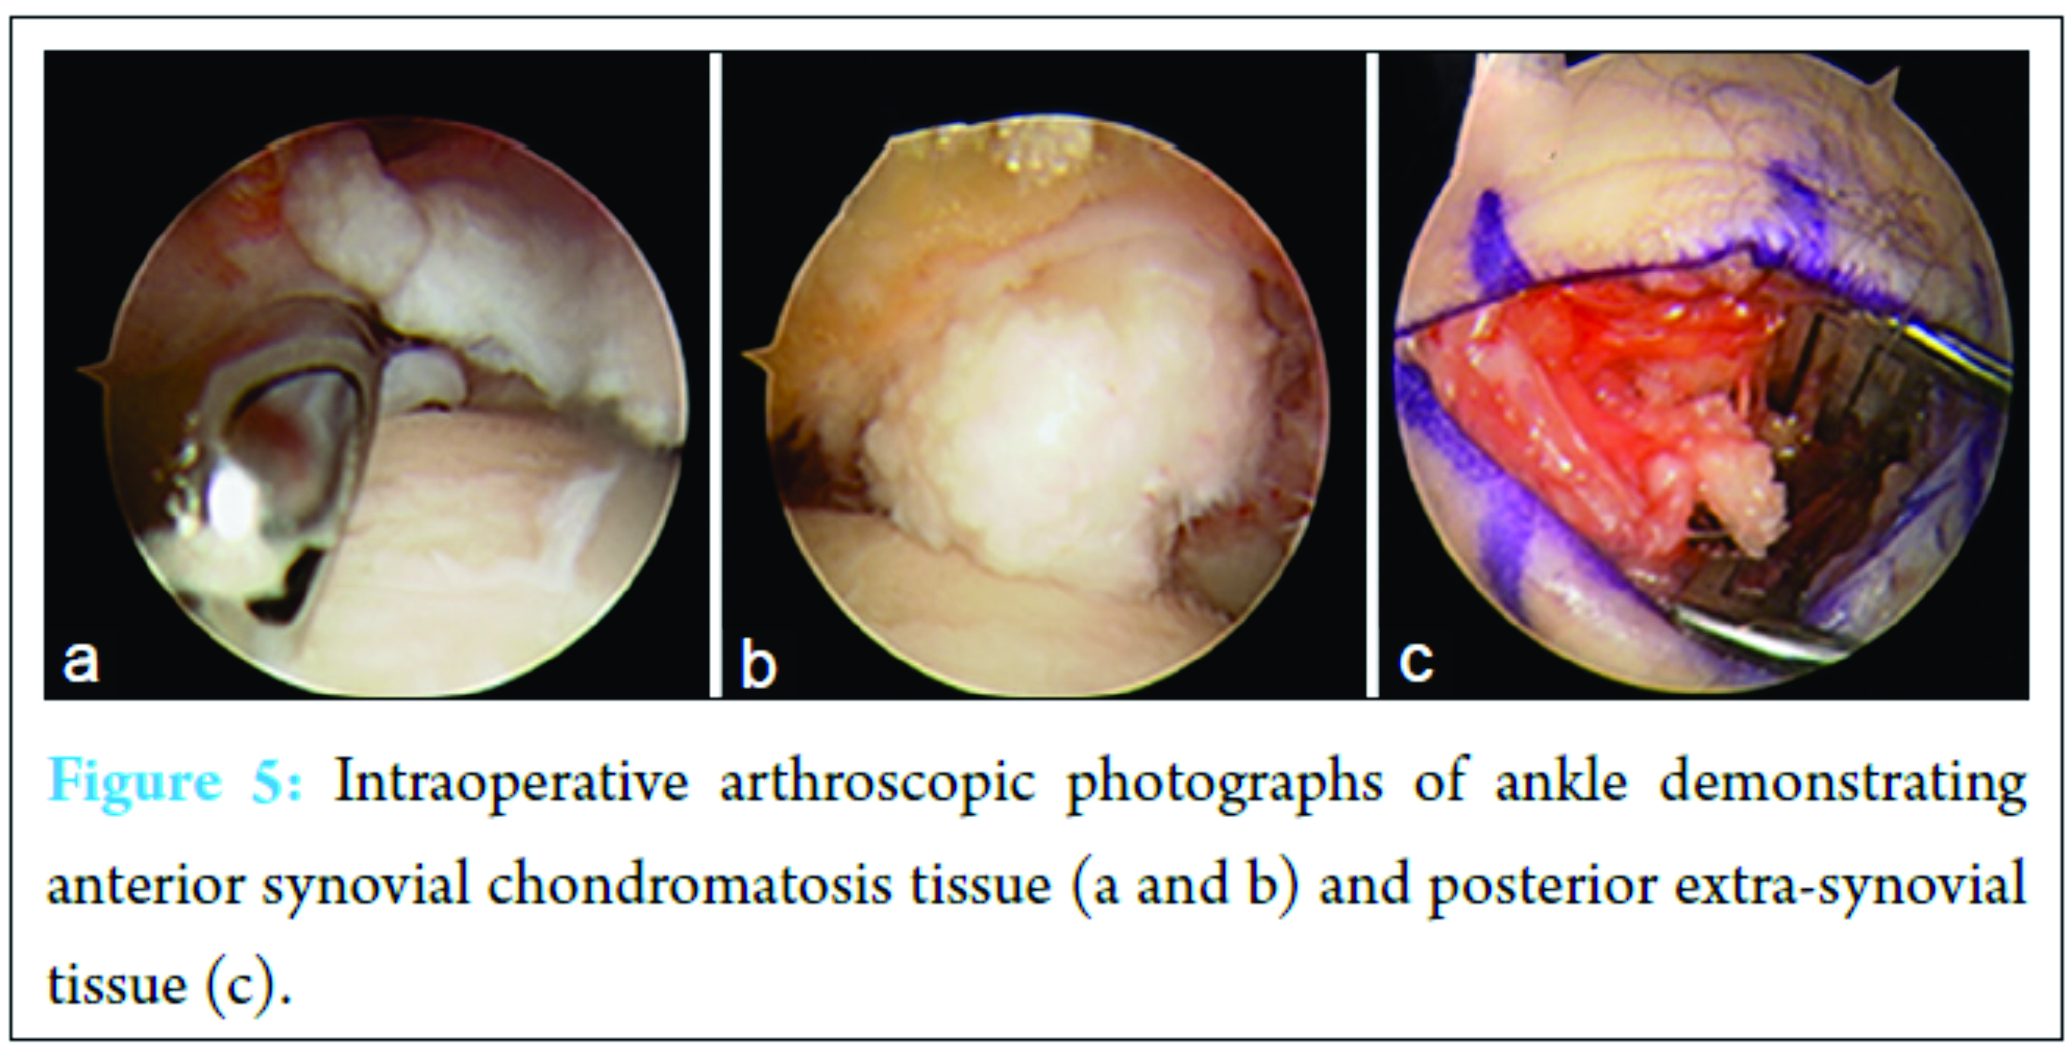

Two years after that first operative intervention, the patient returned with left ankle pain and swelling aggravated by shoe-wearing, weight bearing, and climbing stairs. He also reported symptoms consistent with tarsal tunnel syndrome in the same foot – tingling and burning along the plantar aspect of his foot. Physical examination at this time demonstrated palpable fullness of the ankle joint with minimal restriction in range of motion as well as exquisite tenderness to palpation anterolaterally. A palpable mass was noted along the anterolateral aspect of the ankle. His motor and sensory exams were within normal limits and range of motion of the ankle, and subtalar joints were within normal limits. Radiographs obtained demonstrated opacity overlying the pre-Achilles fat pad and adjacent soft tissues of the posterior ankle (Fig. 1). There was moderate erosion of the anterolateral aspect of the distal tibia. No fractures, dislocations, or intrinsic osseous abnormalities were noted. Ultrasound of the left ankle revealed distention of the joint capsule anteriorly and posteriorly at the tibiotalar joint with intra-articular debris as well as hyperemia of the synovium (Fig. 2). The anterolateral gutter also had intra-articular debris and was distended. Magnetic resonance imagining (MRI) demonstrated numerous large, lobulated, heterogeneously enhancing lesions posteriorly surrounding the flexor hallucis longus (FHL) tendon, and extending into the anterior tibiotalar joint (Fig. 3). There was minimal involvement of the sinus tarsi; however, cranial extension between the distal tibiofibular syndesmosis was noted along with stable erosion of the anterolateral aspect of the distal tibia. The tendons and ligaments of the left ankle were intact, and the articular cartilage was unremarkable. No soft tissue swelling, edema, or bony involvement was identified. These findings were consistent with the MRI findings from his primary presentation 2 years ago (Fig. 4). Extensive ankle joint T2-signal abnormality was consistent with recurrence of synovial chondromatosis. Following this rediagnosis, the patient was scheduled for ankle arthroscopy with joint decompression and synovial debridement.